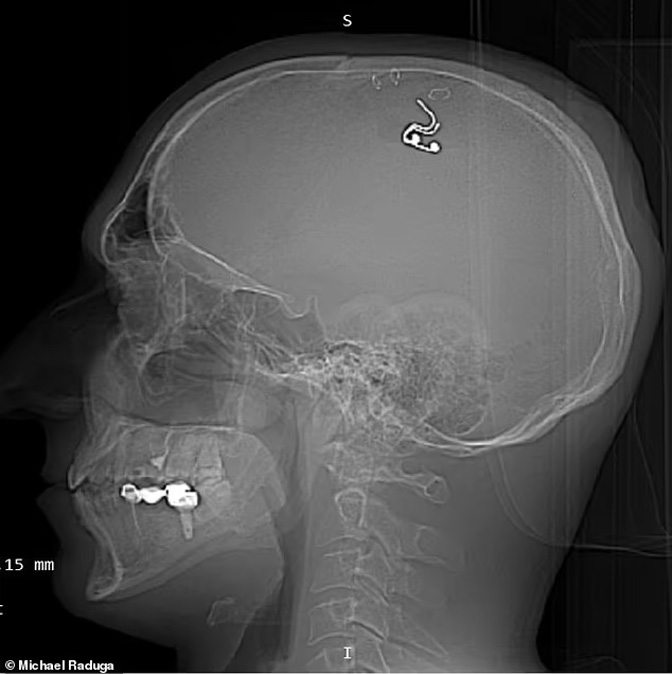

Године 2023. ризиковао је живот покушавајући да угради микрочип у сопствени мозак како би контролисао своје снове.

Мајкл Радуга (Фото: Дејли мејл)

Четрдесетогодишњак, који нема квалификације из неурохирургије, упоредио је свој изузетно опасан експеримент са филмом „Инцепшн“– тврдећи да једног дана може промијенити ток луцидног сањања.

Језиви снимци поступка показују га како држи кожу назад спајалицама док буши потиљак помоћу бушилице коју је нашао у продавници.

Чип је уградио у мозак након што је гледао сате неурохируршких видео снимака на Јутјубу и вјежбао на пет оваца – никоме није рекао о својим плановима.

Чип је на крају уклоњен у болници након пет недјеља.

Чип у глави Мајкла Радуге (Фото: Дејли мејл)

Изузетно опасна студија није објављена у било којем рецензираном часопису и није подржана од стране универзитета, али Радуга је тврдио да је то морао учинити за себе.

„Драго ми је да сам преживио, али био сам спреман да умрем“, рекао је у ексклузивном интервјуу за Дејли мејл прошле године.